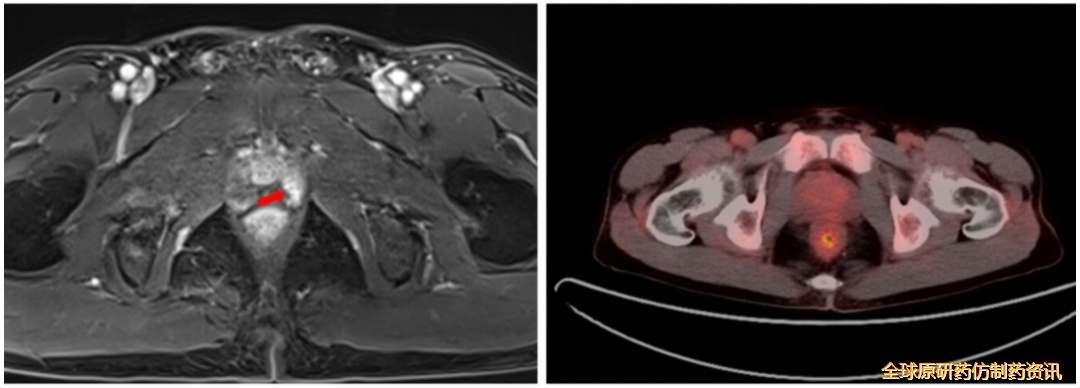

首次消融术后46个月复查(2021.08)

第四次消融1个月后发现前列腺特异性抗原(PSA)升高;

MRI提示前列腺左外叶异常强化灶,考虑恶性肿瘤;

图12 MRI复查结果

于B超引导下经直肠行前列腺穿刺活检术。病理诊断1 号、7 号切片:CK18(+)、CK19(+)、Hepatocyte(−)、CD34(+,显示肝窦毛细血管化);34βE12、AMACR、P63(均−);Ki-67( 3% +)。结合免疫组化结果,符合肝细胞癌转移。